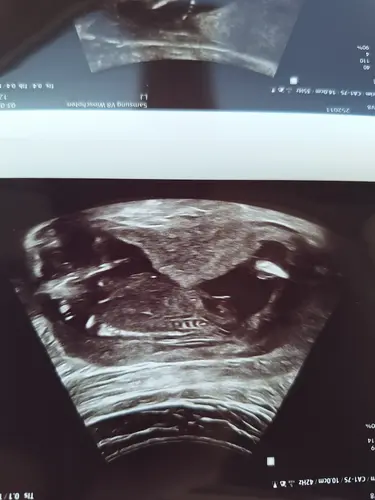

Klopt het dat dit een piemeltje is?

Nee volgens mij wordt hier het bovenbeen gemeten. Ik zie echt geen piemeltje op deze echo. 🫢😵💫

Oh haha ik dacht dat uitsteeksel er tussenin 🤭

Ik moest er nog eens naar kijken. Scherm gedraaid. Ik keek er anders tegen aan. 🫣🤣

Ja ik denk dat je hier idd een piemeltje ziet. 💙🤞